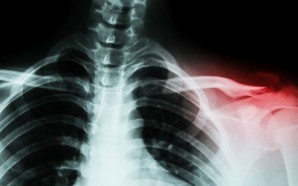

• Bone_web_1024

Your bones could soon heal a whole lot better thanks to polymer nanoshells

Might we one day have bionic body parts able to ward off disease and injury and even heal themselves? Today it’s still the stuff of sci-fi movies, but there are regular breakthroughs in the field of medical science that suggest ...